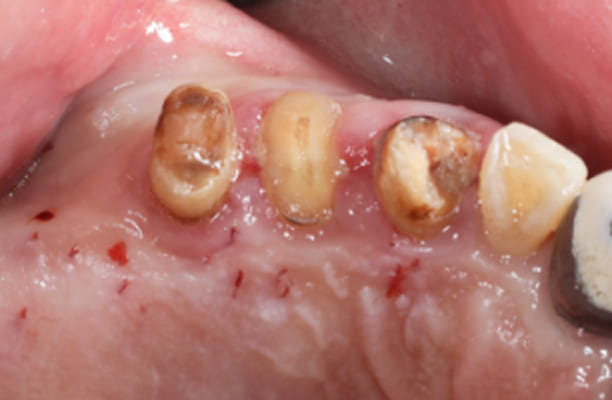

临床案例

-

术前 -

术后